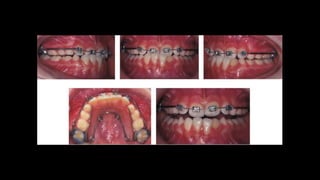

Casos clínicos

4x2